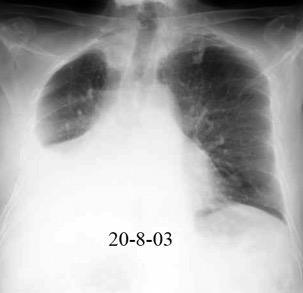

3707 pacientes 29 Derrames (0,78%) > de 25% del hemitórax

Todas menos 2 Izdos.

Angioplastia

By-pass coronario 21-10-03